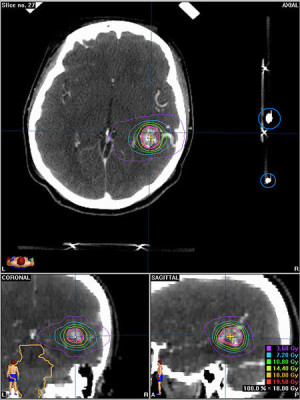

Casos Neuroloquirúrgicos

Envíado por Dr. Ruben Eduardo Amaya Contreras